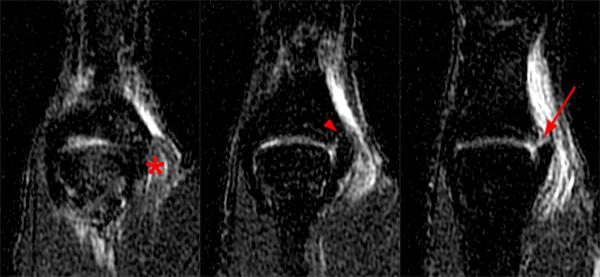

Injuries and problems with this joint are uncommon. The thumb mcp is similar in anatomical appearance to those of the finger,but essentially functions as a hinge or ginglymus joints. Flexion or extension and abduction or adduction.figure 2b shows a schematic illustration of the cmc joint that is superimposed with an illustration of 2 separate hinge joints, one of which allows only flexion and extension and the other only abduction and adduction.

The anatomy of wrist, thumb and hand is complex because of the presence of many different functional joints: The thumb metacarpal can bend and extend the thumb, move the thumb away from and toward the hand, and spin the thumb on the trapezium. Joint replacement artificial implant eorthopod